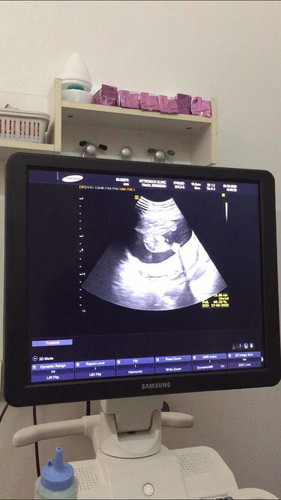

เพศลูก

หมอบอกจู๋ แม่ๆที่มีประสบการณ์ช่วยดูให้หน่อยค่ะ ว่าตรงลูกศรชี้ใช่จู๋เหมือนที่หมอบอกมั้ยคะ ☺️

ขออนุญาตเอารูปจุ๊ดจู๋เจ้าตัวน้อยมาแชร์นะคะ ☺️ ตอนนั้นวันที่19เดือนที่แล้ว 22w3d ค่ะ

บ้านนี้ท้องแรกเห็นปิกาจู้ ตั้งแต่ 13วีค เลยค่ะ ส่วนใหญ่ เพศชายจะๆม่ค่อยพลาด

ดูไม่ออกเลย ลองซาวน์อีกครั้งตอน 24 สัปดาห์ จะชัดมาก

น่าจะผช.ตามหมอบอกนะคะแม่